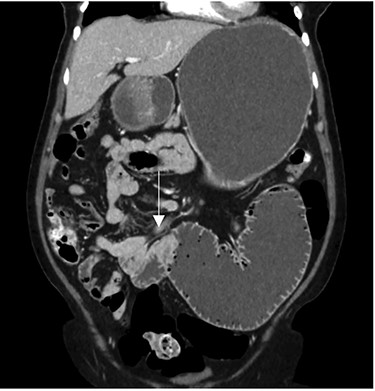

After clinical evaluation, the patient underwent computed tomography (CT) of abdomen and pelvis with IV contrast, which revealed fluid-filled esophagus, dilated stomach and first part of the small intestine with a transition point in the mid jejunum (Fig. 1). Her proximal small bowel, stomach and esophagus were significantly distended. She was subsequently decompressed with a nasogastric tube. For further delineation of this transition point, a magnetic resonance imaging (MRI) was performed, which confirmed a narrowed lumen secondary to an intrinsic mass of the jejunum (Fig. 2). Later, she underwent exploratory laparotomy with an evident transition point found at 30 cm from the ligament of Treitz (LT) (Fig. 3). We performed a partial small bowel resection and side-to-side stapled anastomosis. The rest of the bowel appeared healthy; there was no evidence of serosal involvement or extension to surrounding loops of bowel. Multiple enlarged lymph nodes were identified in the mesentery.

CT imaging—coronal view showing the transition point in the jejunum.